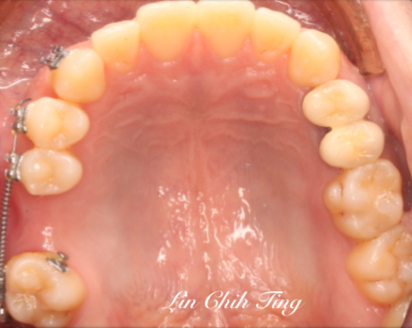

矯正治療過程

治療前

治療中